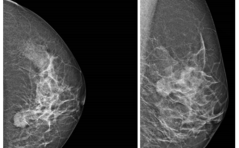

Seltene benigne Tumore der Mamma PDF Dokument